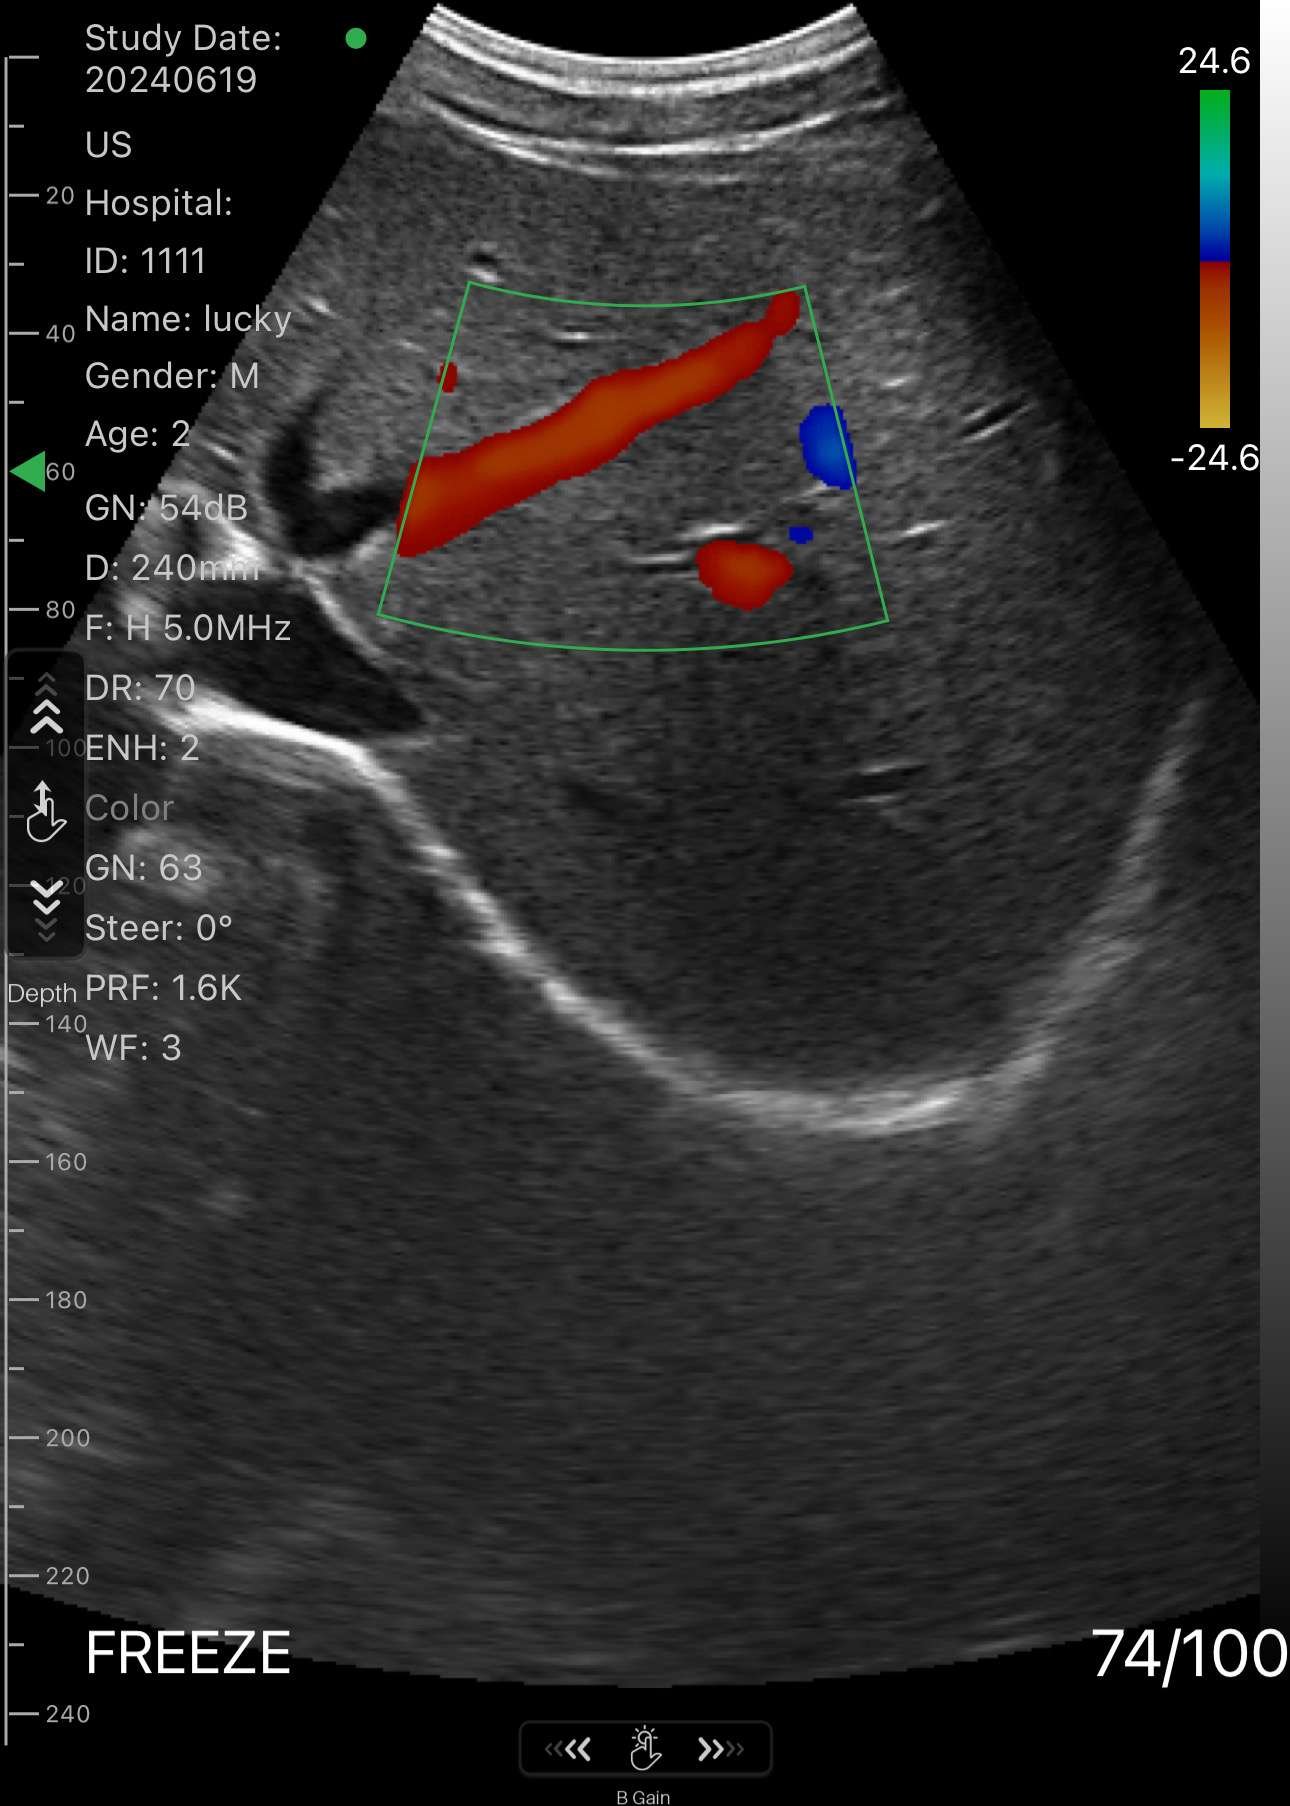

Convex Ultrasound Probe

Unlock Clear, Deep Imaging with the Convex Ultrasound Probe – Trusted Versatility for Everyday Diagnostics

The Convex Ultrasound Probe is your go-to solution for high-resolution abdominal and pelvic imaging, delivering deep tissue visualization with exceptional clarity. Designed for both general practitioners and specialists, this portable, user-friendly probe is perfect for OB/GYN, urology, emergency medicine, and internal diagnostics.

Whether you're performing liver scans, monitoring fetal development, or assessing kidney and bladder health, the Convex Probe offers wide scanning coverage and precise results — all from a compact, reliable device.

Take diagnostic confidence to the next level with a tool that blends portability, performance, and clinical accuracy.

- Switch between B,B+B, B/M, Color, PW, PDI, B+Color+PW

1. Abdominal Imaging

- Assess organs such as the liver, gallbladder, pancreas, spleen, and kidneys.

- Detect abdominal masses, fluid collections, or organ enlargement.

- Evaluate abdominal pain, jaundice, or trauma-related injuries.